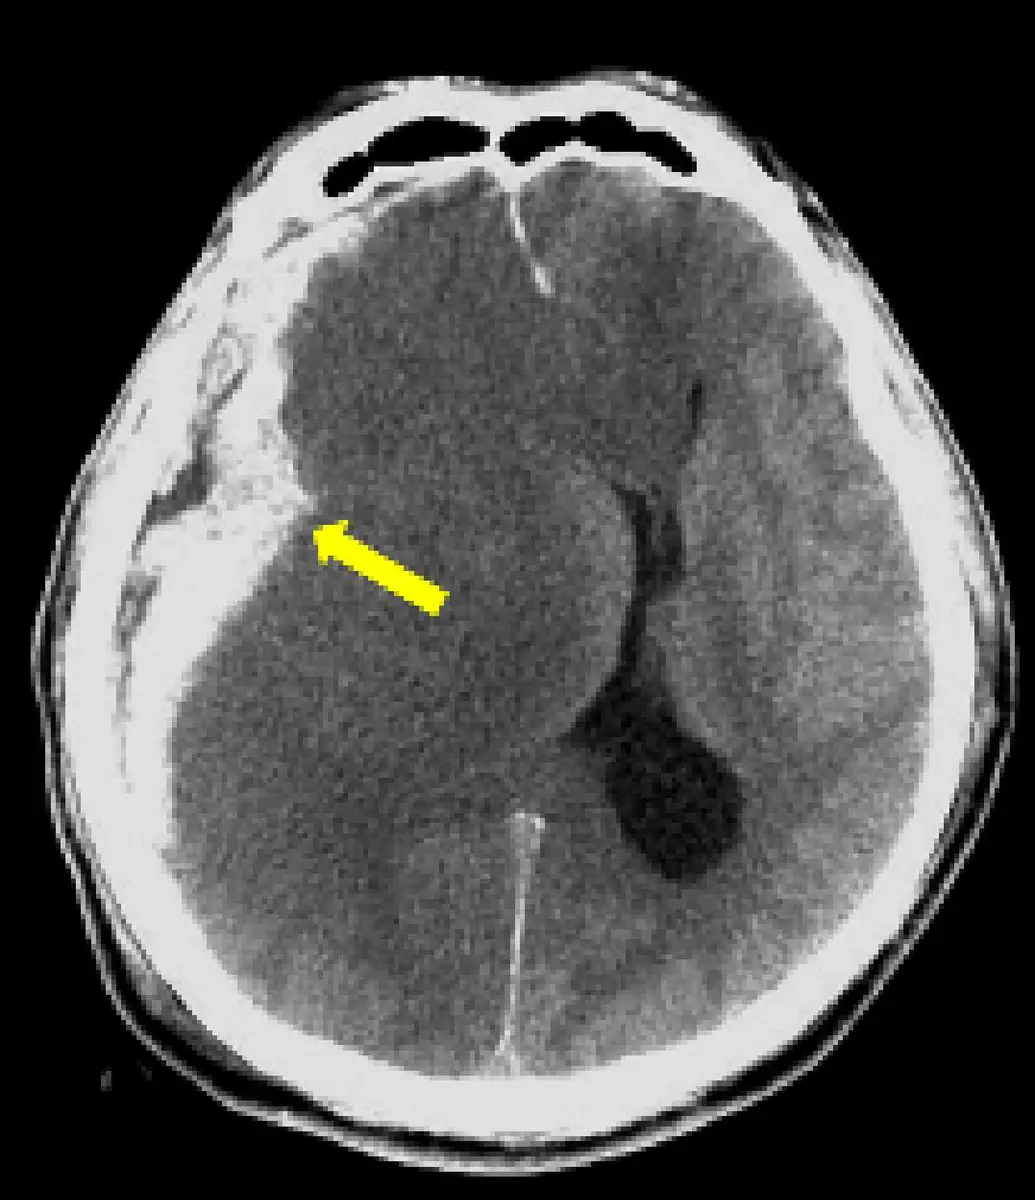

如圖箭號所指,診斷為何?

- 影像類型:腦部 CT 橫斷面(axial view)

- 箭號所指:右側大腦半球外側,緊鄰顱骨內板,呈現一月牙形(crescent-shaped)高密度影(hyperdense collection)

- 分布特徵:血腫沿顱骨內板走行,邊界呈內凹弧形(concave toward the brain),向腦實質方向凹陷

- 跨縫特性:病灶跨越骨縫(suture lines),未受骨縫限制

- 佔位效應:右側大腦半球受壓,腦中線向左偏移(midline shift to the left),顯示明顯佔位效應

- 右側側腦室:受壓縮小

上述影像特徵高度符合**急性硬膜下腔出血(acute subdural hematoma)**的典型表現。